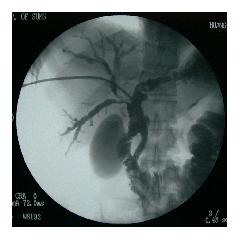

(八)、经皮肝穿胆道造影及引流术(PTCD)

胆道支架置入术:是消化内科诊治梗阻性黄疸的另一种微创技术,通过经皮经肝途径下行操作,更加简捷、灵活,解决复杂胆道问题,如肝内胆管、肝门部胆管病变等,可弥补ERCP技术不足或与之相配合,相得益彰,为患者提后供了另外一种选择。